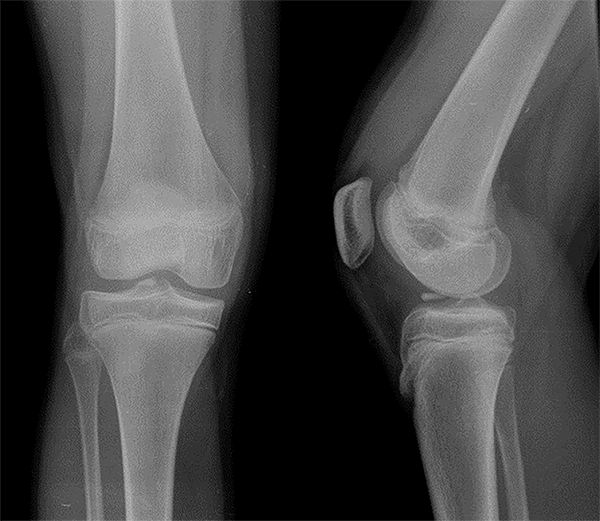

La radiografía anteroposterior mostró una imagen radiopaca a nivel del intercóndilo y la espina tibial que hizo sospechar una avulsión de esta última (fig. 2). Se solicitó una RM de rodilla que evidenció una espina tibial continua y ninguna lesión evidente en la articulación.

Figura 2. Rx de rodilla derecha frente y perfil. Imagen radiopaca que impresiona avulsión de espina tibial.